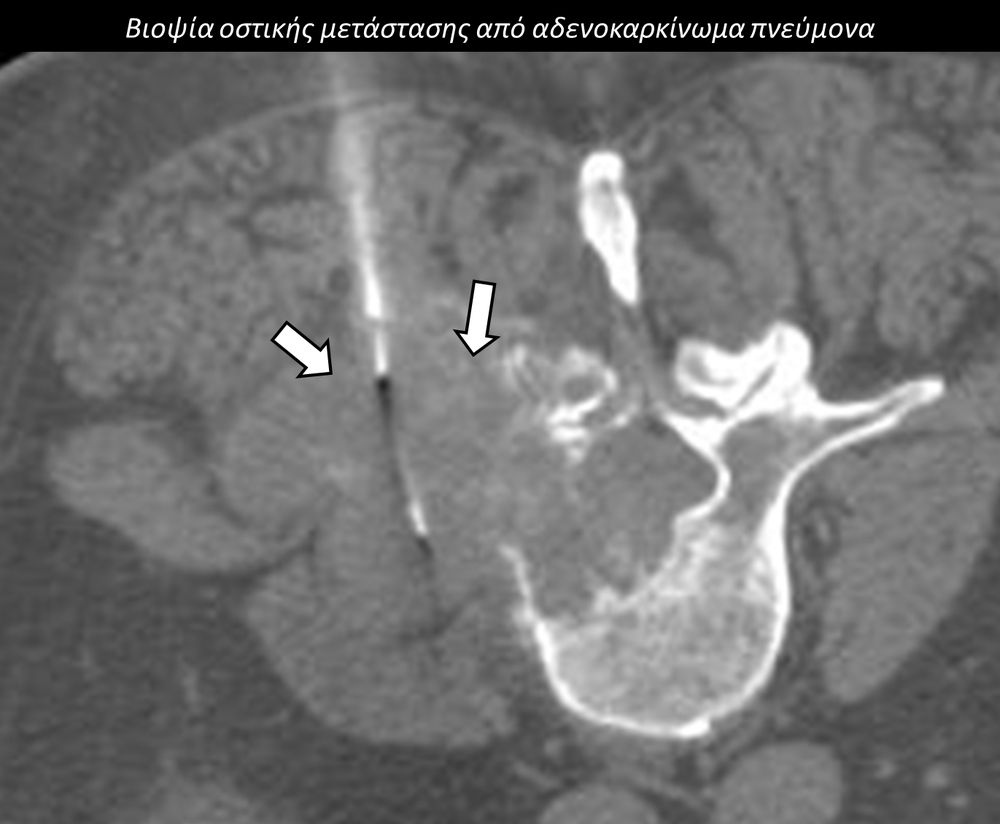

Η διαδερμική βιοψία είναι μία ελάχιστα επεμβατική μέθοδος λήψης υλικού από τον όγκο για κυτταρολογική και ιστολογική εξέταση, από εστιακές αλλοιώσεις του ήπατος, πνεύμονα, νεφρού κλπ. Συστήνεται από τον κλινικό ιατρό ανάλογα με το είδος και το μέγεθος της βλάβης και πραγματοποιείται με ασφάλεια από επεμβατικό ακτινολόγο με την καθοδήγηση αξονικού τομογράφου ή υπερήχων. Στη σύγχρονη ογκολογική θεραπεία όπου γίνεται προσπάθεια καταπολέμησης του καρκίνου σε μοριακό επίπεδο κρίνεται αναγκαία η ακριβής ιστολογική ταυτοποίηση του όγκου ώστε να εφαρμοσθεί εξατομικευμένη θεραπεία για το βέλτιστο αποτέλεσμα. Οι κατευθυνόμενες βιοψίες στοχευουν στο να παρέχουν στον κλινικό ογκολόγο το απαραίτο ιστοπαθολογικό υλικό που θα του επιτρέψει να εφαρμόσει την κατάλληλη θεραπεία για τον ογκολογικό ασθενή.